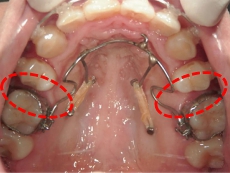

臼歯にリンガルアーチという装置を装着し、ミニインプラントを固定源に臼歯を後方に牽引します。

臼歯が後方に下がり、臼歯と小臼歯の間にスペースができました。唇側にワイヤ-をSETし、前歯の歯並びの改善を併行して行います。